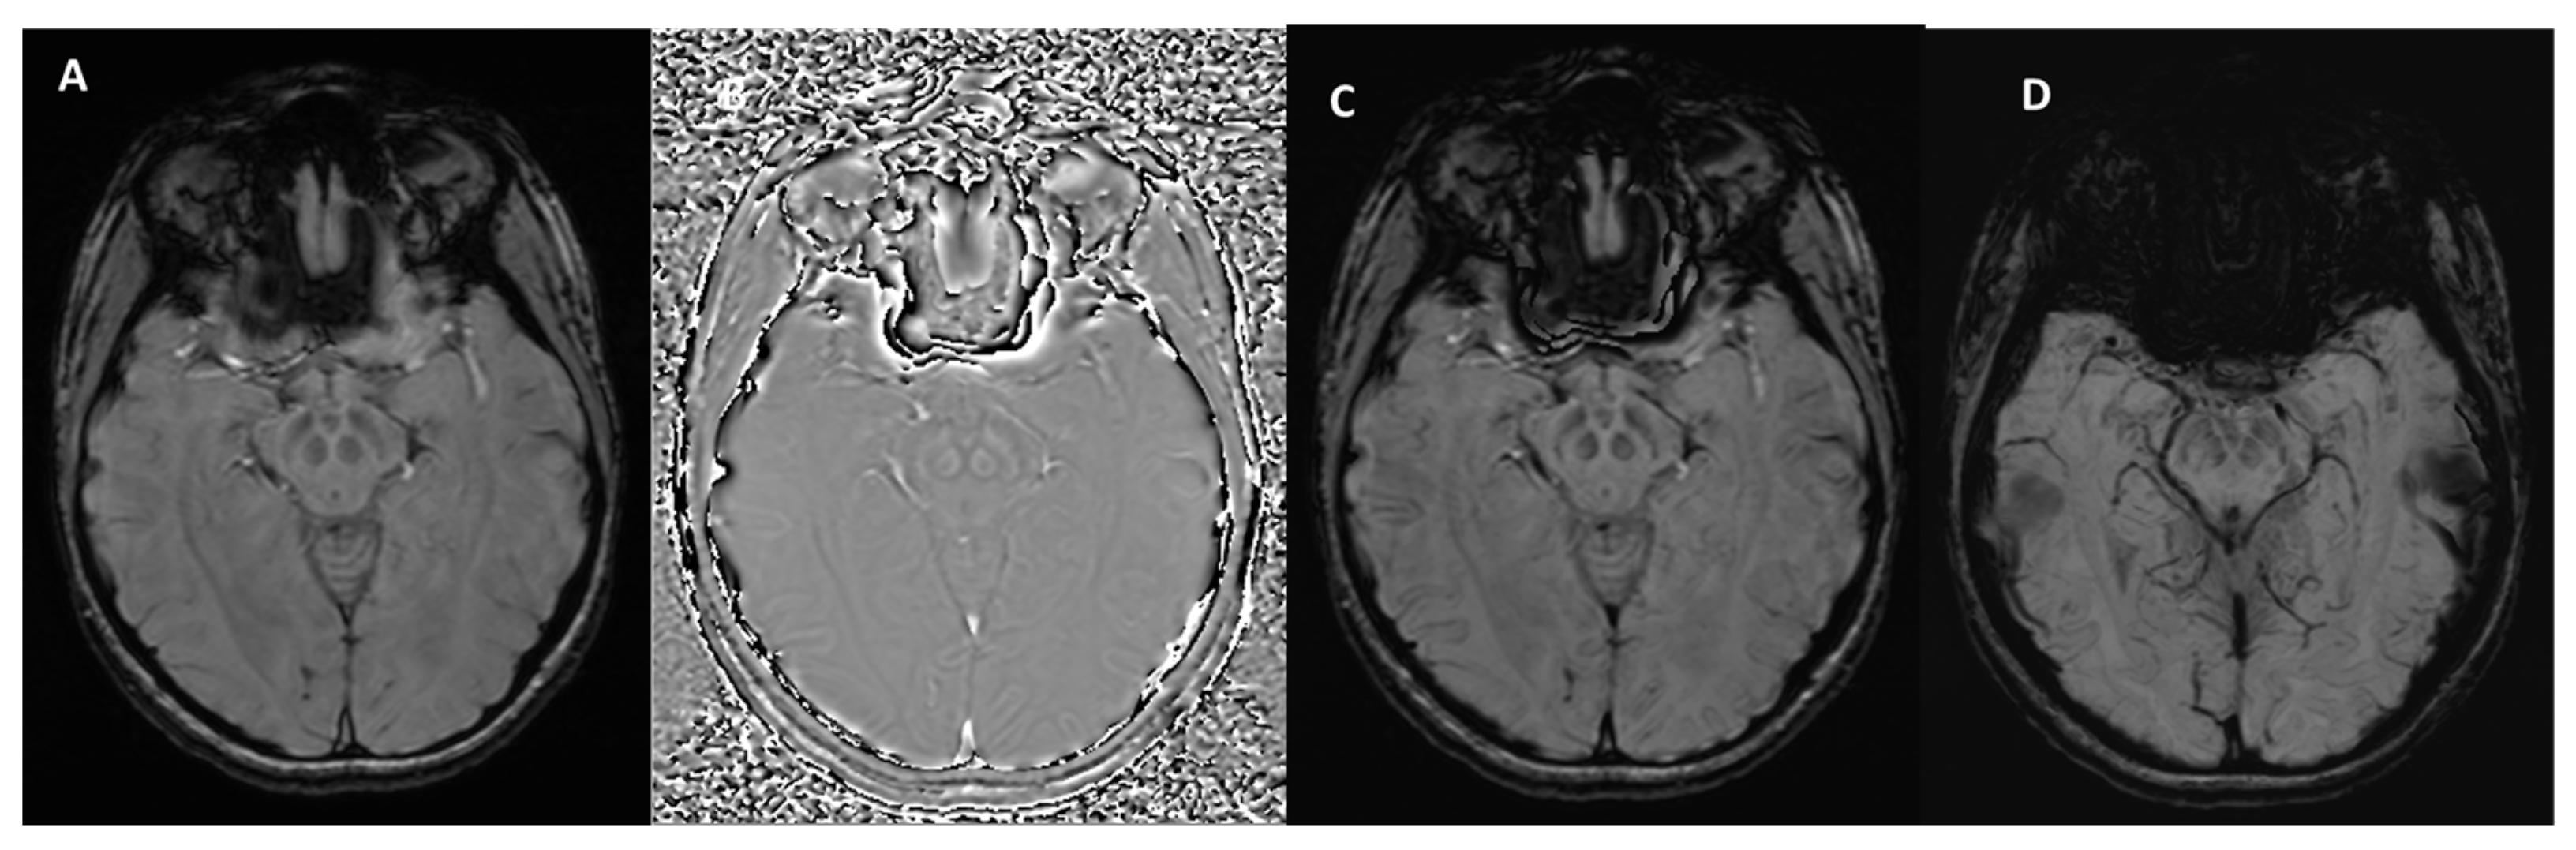

- Yaghmaie, N.; Syeda, W.T.; Wu, C.; Zhang, Y.; Zhang, T.D.; Burrows, E.L.; Brodtmann, A.; Moffat, B.A.; Wright, D.K.; Glarin, R.; et al. QSMART: Quantitative susceptibility mapping artifact reduction technique. NeuroImage 2021, 231, 117701. [Google Scholar] [CrossRef]